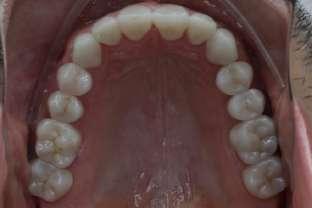

Si presenta alla nostra attenzione un paziente maschio, 35 anni, in apparente salute sistemica, fumatore, con la richiesta di controllare delle white spots, una leggera sensibilità e la richiesta di migliorare la luminosità del suo sorriso. Viene compilato e firmato il consenso informato. Il paziente viene motivato ad più efficace controllo del biofilm batterico e attraverso la condivisione dell’immagine clinica della topografia del biofilm batterico, (T.B.M.) scegliamo lo scovolino in gomma GUM Soft-picks (Sunstar) e lo sollecitiamo all’uso efficace degli spazi sovracrestali e allo spazzolamento in maniera delicata ma efficace della lingua. Sottoponiamo il paziente alla terapia parodontale non chirurgica con ablatore Comby touch (MECTRON) in modalità soft-mode per contenere la sua sensibilità. Valutiamo la sensibilità e modifichiamo i suoi stili di vita di igiene orale, di igiene alimentare e chiediamo di smettere di fumare. Il paziente riferisce di non essere disposto a rinunciare al fumo e chiediamo di ridurre il rischio di patologie e di discromie

da tabagismo passando all’uso dei dispositivi a tabacco riscaldato. Successivamente rileviamo il colore, con spettrofotometro, e con scala-colori Vita e documentiamo fotograficamente la condizione clinica presente.

Il colore rilevato è A2. Sottoponiamo il paziente ad uno sbiancamento pro-

fessionale con un principio attivo PAP (acido ftalimidoperossicaproico) che presenta il vantaggio di non sollecitare la sensibilità, pur mantenendo l’aspettativa di un risultato efficace nell’ottenere la luminosità del sorriso. Lo sbiancante ad uso professionale BRILLIANT LUMINA (Coltene), risulta essere per l’operatore di facile applicazione: ven-

gono protette le gengive con la diga liquida fotopolimerizzata, e si mescola il gel sbiancante lasciando cadere nel vasetto contenente 2 ml di gel, 3 gocce di liquido attivatore. Si ottiene il gel sbiancante di una consistenza ideale per una applicazione sulle superfici dentali sicura e pratica durante l’apposizione. Vengono eseguiti 4 step da 15 minuti.

Dopo ogni step viene aspirato il gel, pulite le superfici dentali con del cotone idrofilo e si riappone nuovamente il gel. Al termine dei 4 step, si aspira, si asciuga e viene tolta la diga. Si rileva e si condivide con il paziente il risultato ottenuto, A1, e viene documentato fotograficamente. Il paziente appare gioioso del risultato è favorevolmente colpito di non aver sofferto durante il trattamento di sensibilità. Alla persona assistita sono stati programmati dei follow-up per il trattamento successivo delle white spots con applicazioni di resine infiltranti e rigenerazione guidata dello smalto.